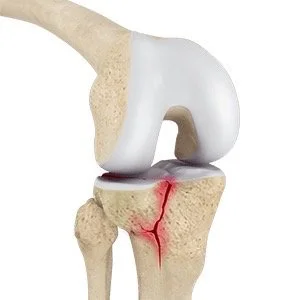

Tibial plateau fractures occur at the top of the tibia, often resulting from high-energy trauma such as falls or automobile accidents. These fractures can disrupt the integrity of the knee joint, leading to pain, swelling, instability, and limited mobility. Depending on the severity and displacement of the fracture, treatment options range from conservative measures like immobilization and physical therapy to surgical interventions such as open reduction and internal fixation (ORIF) or TKR.

What is a tibial plateau fracture